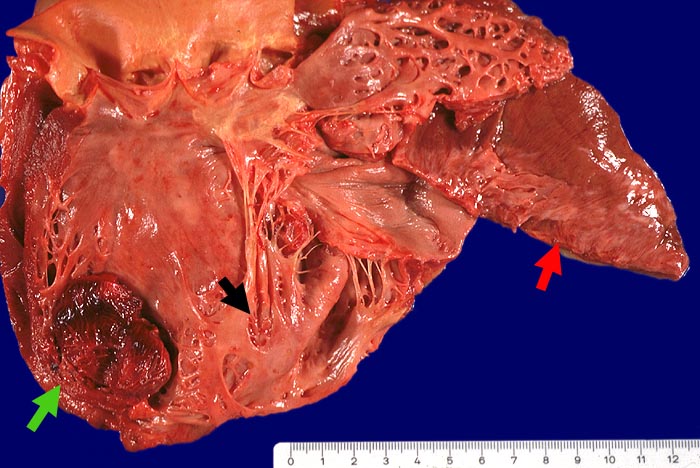

PathoPic – image database / PathoPic ID 2088 - Thrombosiertes Herzwandaneurysma, Myokardinfarktnarbe

Thrombosiertes Herzwandaneurysma, Myokardinfarktnarbe

Myokardinfarktnarbe der Hinterwand, der Vorderwand und des Septums (14x8cm). Thrombosiertes Herzwandaneurysma des Septums (4x8cm)im Bereich der Narbe. Abrundung der Herzspitze und Vergrösserung des Herzens (exzentrische Hypertrophie).

Schwere stenosierende Sklerose des Ramus interventricularis anterior der linken Koronararterie.

St.n. Myokardinfarkt vor 3 und 10 Jahren. Low-Output-Syndrom.